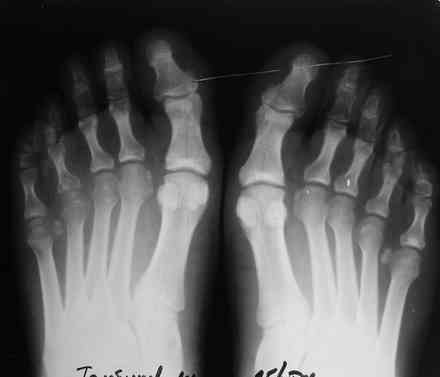

Уважаемые коллеги. Помогите определиться с диагнозом. Мужчина 28 лет обратился с жалобами на боль в правой стопе, усиливающиеся с утра "пока не расходишься".

Боль беспокоит на протяжении 4 мес, Имеется незначительная припухлость. болезненность при пальпации головок 4,5 плюсневых костей справа, кожа не измененена. Лабораторные данные в пределах нормы, хронических инфекций нет. рентгенологически имеется остеопороз головок 4,5 плюсневых костей справа.

Здравствуйте Максим! Вполне возможно, что это остеохондропатия по типу болезни Келлера 2 в начальной стадии.

там же вроде II -III плюсневые поражаются, чаще у молодых женщин.

-Симметричное поражение

очень напоминает ревматоидный полиартрит, направьте к ревматологам. как ортопеду причин для вмешательств пока нет.

в том то и дело, что асимметричное, только головки 4,5 справа, все остальное не беспокоит

Максим. Это может быть одно из заболеваний из группы патологий серонегативного спондилеартрита. Кроме того надо исключить Мортоновскую стопу.